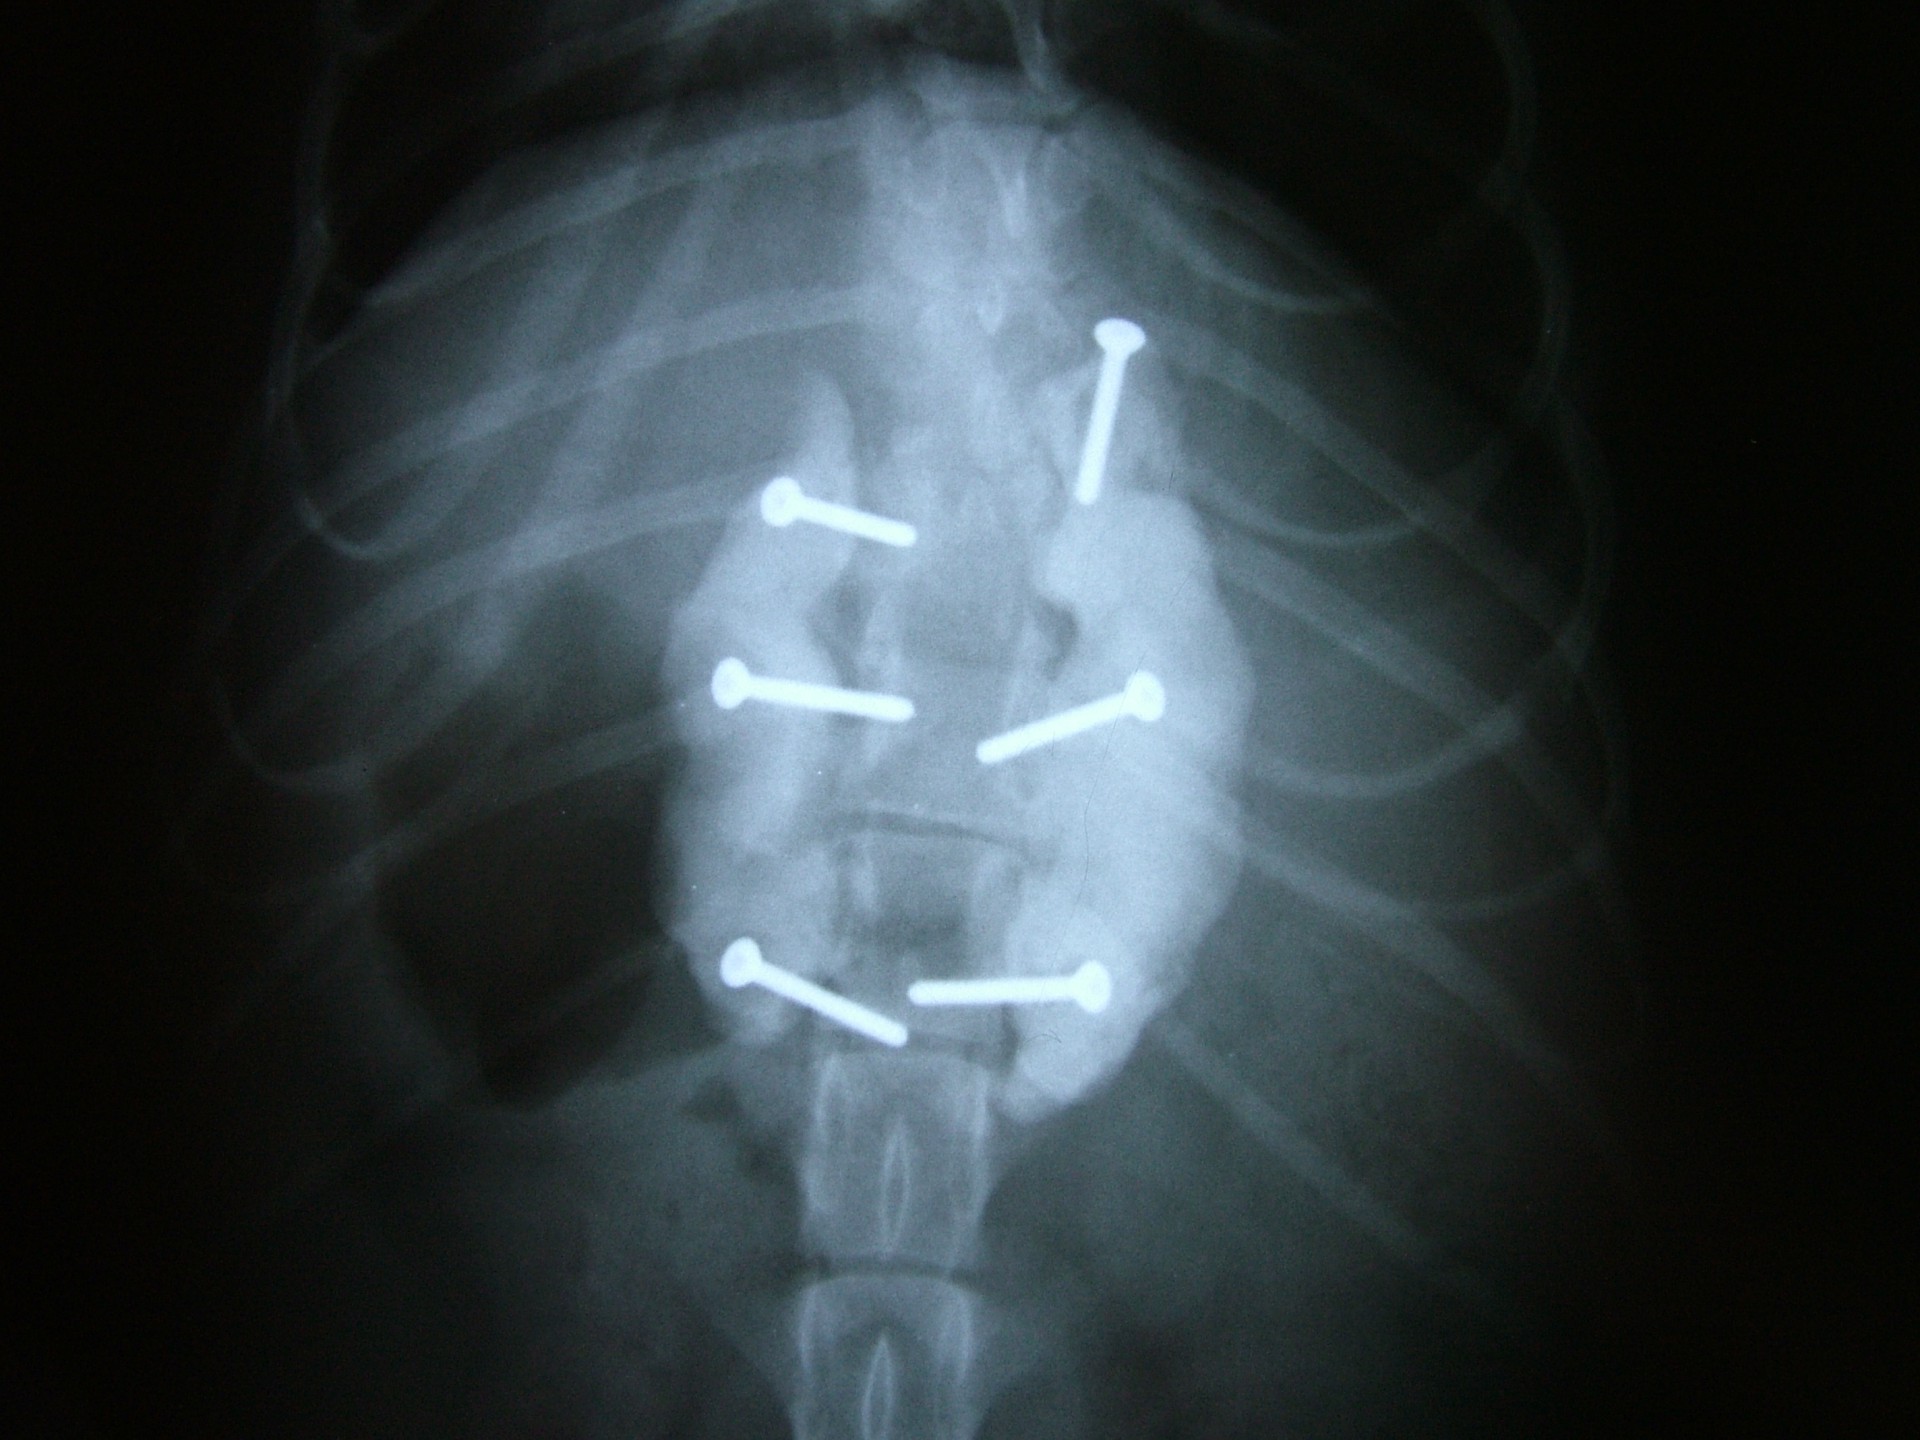

A törött csigolyatestek adaptációja és rögzítése a nyitott gerinccsatorna mellett komoly kihívást jelent. A későbbi elmozdulás elkerülésére többféle műtéttechnika alkalmazható, melyek közül a csigolyatestek lemezes osteosynthesise ill a fixateur interna használata terjedt el leginkább. Első esetben a sérülés előtti és mögötti csigolyákat lemez és csavarok segítségével egymáshoz rögzítjük, míg az utóbbi esetben a törés előtti és mögötti egy vagy több csigolyatestet két oldalról behelyezett csavarok és egy steril kétkomponensű akrilát műgyanta segítségével rögzítjük.